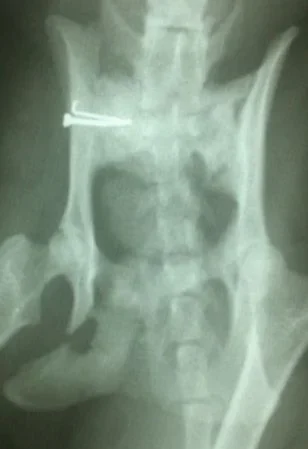

Galería de casos clínicos

Casos clínicos de cirugía (tejidos blandos, traumatología, neurocirugía, artroscopia)